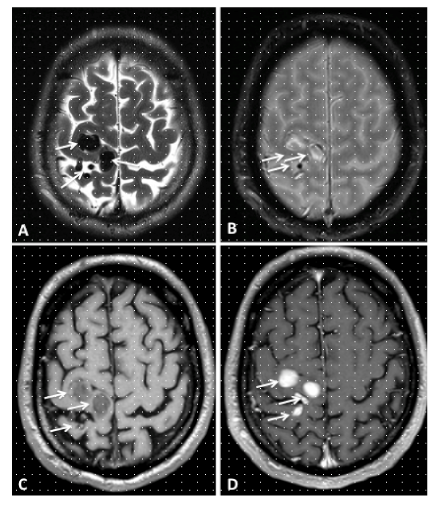

Figure 5 A 33year old man presenting with sudden headache and meningiomes. A. Axial Head CT scan shows a pialhemorrhage (white Arrow) on the surface of the right anteriorquadrangular lobe of the cerebellum. B. Axial T1-weighted enhanced MRI showing a small flow void in contact with the right posterior 1/3 of the free tentorialedge, corresponding to a suspended veinbridgingbetween the tentorialconvexity of the cerebellum to a tentorialvenouslacuna. C. Coronal T2-weighted High resolution image, showing the bridgingvein (white Arrow). D. Sagittal T1-weighted reference image. The yellow trait corresponds to the level of the coronal cutdepicted in the C box. AP and F, LL views of DSA, showing a grade III Borden without venous ectasia, Grade III Cognard IDAVF supplied by the right tentorialartery (Bernasconi and Cassinariartery, white arrowhead), branch of the meningohypophisealtrunk, originatingfrom the intracavernous ICA and drained by the small suspended vein (white arrow) tributary of a tentorialvenouslacunaseen on MRI, whichis the source of hemorrhage.

Figure 6 A 50year old man presenting with left partial rolandic seizures. A, T2, B, T2*, C, T1-weighted MR sequences before and D, after gadolinium injection, axial view, showing flow voids (white arrows) without haemorrhage in the right rolandic area.